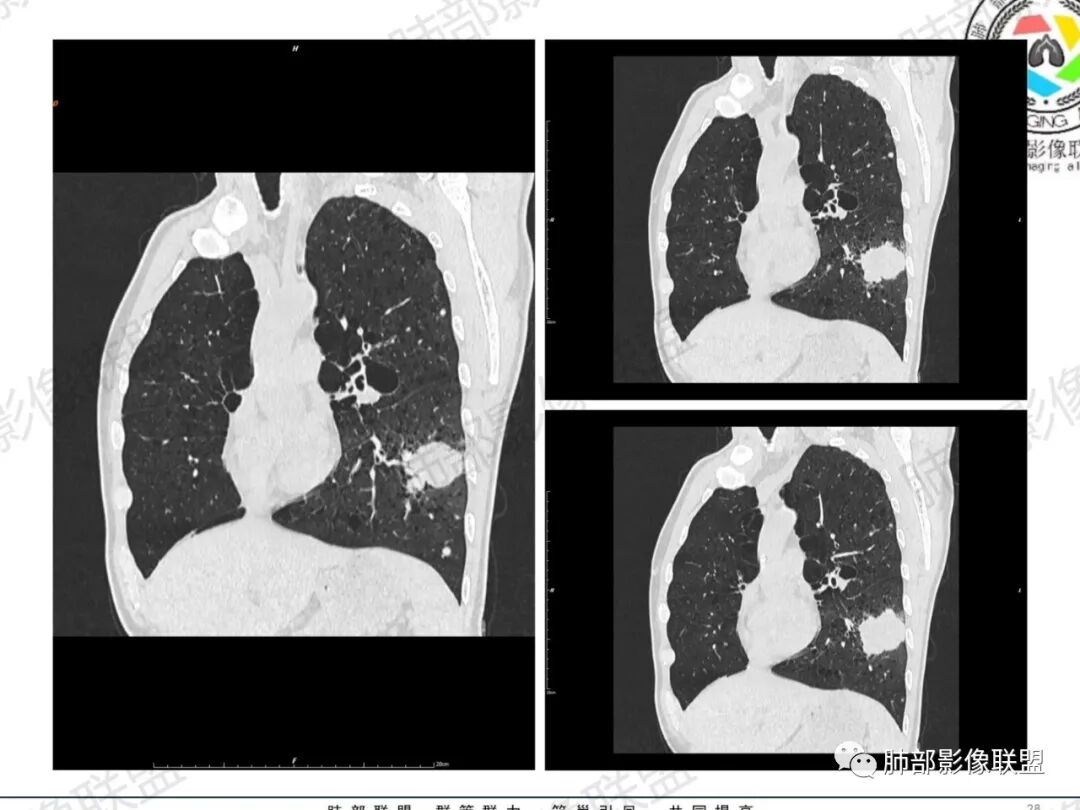

一切∮随缘:左肺下叶不规则肿块,边缘光滑,平直,局部彭隆,分叶,近端支气管堵塞,远端与胸膜相贴,平扫密度尚均匀,增强后不均匀强化,内部可见低密度坏死,胸膜下多发肺气肿,伴双肺散在光滑小结节,实验室肿瘤标志物高,考虑恶性:神经内分泌癌(大细胞),腺癌,鳞癌。

琦遇:恶性没有问题,肺气肿底子、病灶分叶、少许毛刺、叶间胸膜凹陷、部分边缘可见清晰的GGO、胸膜牵拉凹陷、局部胸水、近端支气管截断、部分支气管被推移、占位效应明显、强化特点为不均匀强化、内部有少许沼泽样低强化区,强化部分轻中强化为主、余肺可见转移性结节、左肺上叶似为囊腔型腺癌一枚,肿瘤标志物提示非小、神经内分泌,综合分析考虑大神泌、腺癌、腺鳞癌、鳞癌  同时左肺上叶囊腔型腺癌  肺转移

蕊:中老年男性,吸烟史,肺气肿背景,左肺上叶类圆形肿块影,边界清晰,边缘凹凸不平,有分叶,支气管进入阻断,临近胸膜栽赃,整体病灶膨隆,局部周围可以清晰ggo,临近叶间裂内凹,轻度强化,并可见多个低密度区,坏死可能,界线不清;肺内多结节,边缘光滑,考虑恶性伴转移,鳞癌、腺癌

傅昌瑜:中老年男性,肺气肿背景,右胸背疼痛1周。CEA、NSE、CYFRA—211升高。左上肺混合磨玻璃结节,内见较多空泡和扩张支气管。左下肺胸膜下肿块,边缘较光滑,深分叶,似有血管进入,与支气管关系不清,内见不均匀强化,见沼泽地样坏死,有胸膜栽赃。另两肺多发圆形小结节。考虑恶性并肺内转移,多原发可能性大,左上肺腺癌,左下肺病理难以判断,小细胞癌?鳞癌?

小锁:中老年男性,肺气肿背景,右胸背疼痛1周。CEA、NSE、CYFRA—211升高。左上肺混合磨玻璃结节,边界清楚,内见较多空泡。左下肺肿块,边缘清楚,深分叶,有血管和支气管进入,胸膜凹陷。另两肺多发圆形小结节。考虑双发原位癌,左上肺腺癌,左下肺大神泌或腺鳞癌可能,肺内转移。

蓝天白云:中年男性,肺气肿背景,左肺下叶肿块,边缘膨隆,有分叶,内有湖泊样坏死,有轻中度强化,局部胸膜栽赃,收缩力不强,周围见肺气肿征象。左肺上叶混合磨玻璃影,边界清楚,考虑都是恶性,左上肺iac,左下肺腺鳞癌,或大细胞肺癌可能。两肺多发结节,考虑转移

周太狼:中年男性,吸烟、高血压史,肿瘤指标升高,肺气肿背景下,左肺下叶肿块影,分叶、膨隆、未跨叶裂,支气管截断,不均匀强化。另双肺多发结节及磨玻璃影,左肺上叶混合磨玻璃,内可见多发空泡影。整体考虑恶性,肺癌伴肺内转移,左下肺鳞癌?神经内分泌癌?左肺上叶囊腔腺癌?